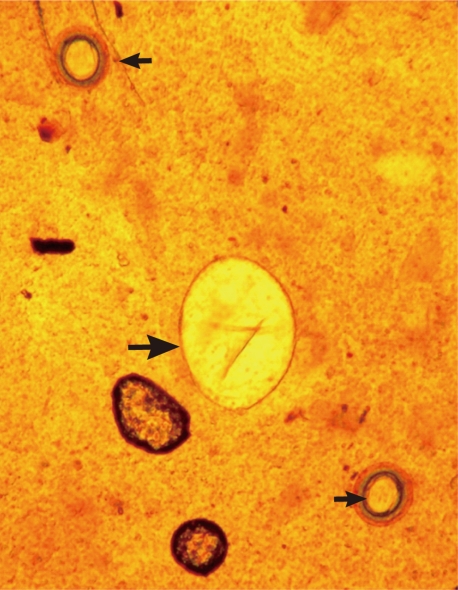

Figs. 3,

4) were 94 µm long (89-99 µm) and 55 µm wide (52-58 µm) (n=10), and had a relatively wide, somewhat inconspicuous operculum, a thin and refractile shell, and abopercular wrinkles terminally. In Kato Katz fecal smears, the operculum and abopercular wrinkles of the eggs are less apparently seen (

Fig. 4).

Fig. 3An Echinostoma ilocanum egg (99×56 µm; larger arrow) and 2 Taenia sp. eggs (small arrows) detected in a Kato-Katz fecal smear of a patient. ×200.